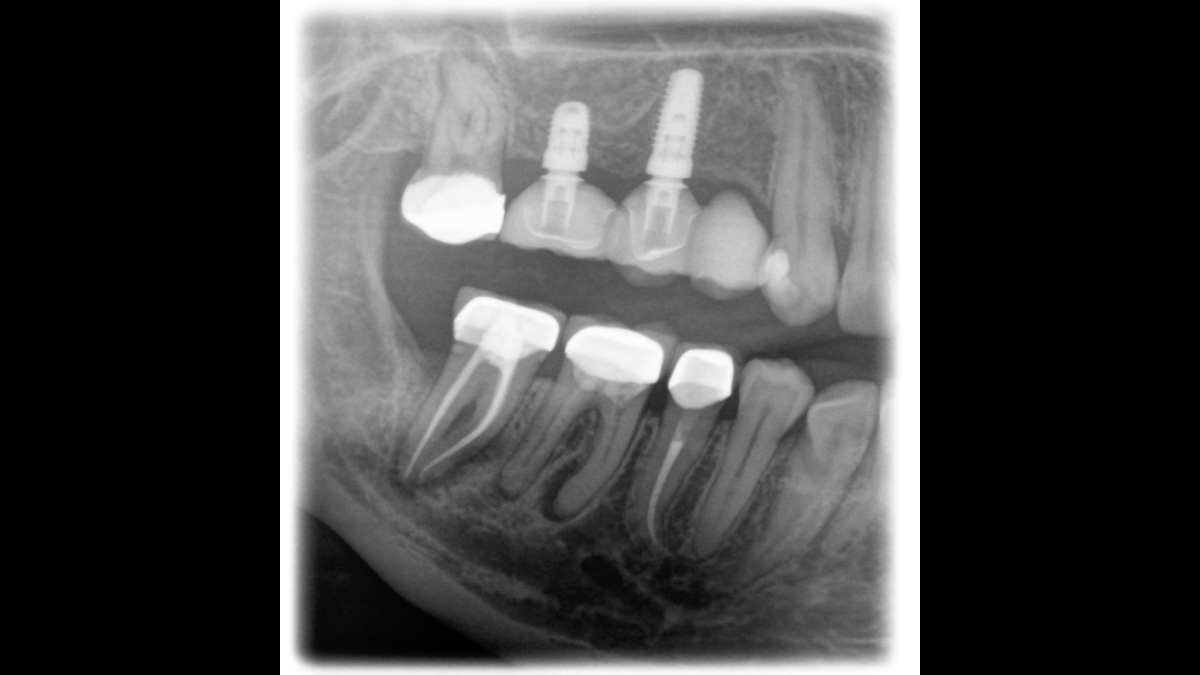

The high-quality 2D/3D X-ray device with a comprehensive range of services for every practice. Whether as a pure 2D device or including a 3D module – the Orthophos S is a reliable partner and optimized for everyday tasks. Its CsI Plus sensor with autofocus function ensures clear images, even in anatomically difficult cases. The automatic patient positioning together with the patented occlusal bite block enables an easy and timesaving patient positioning. For use in orthodontics, the Orthophos S is also available with an optional ceph arm. And because future-proofing is important to Dentsply Sirona, the cephalometric arm can be retrofitted at any time.

With the 3D Intelligent Low Dose mode, you get 3D images in the dose range of a 2D X-ray. In HD mode (up to 1,400) individual images are captured during a single rotation and converted into a 3D volume with up to 80 μm for low-noise images in high resolution.

The right focus is crucial for excellent panoramic radiographs. With the autofocus function you will automatically receive an image with the best possible sharpness in focus. The Orthophos S creates several thousand individual images in one revolution and automatically recognizes the areas in which the jaw is optimally positioned. A sharp panoramic image is created from the individual projections – without any manual intermediate steps.